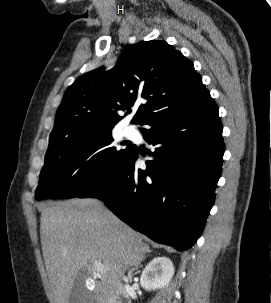

Мультиспиральная компьютерная томография – это современный высокоинформативный рентгенологический метод диагностики различной патологии легких. КТ основана на применении рентгеновского излучения. Однако в отличие от обычного рентгена, при котором снимки делаются в одной плоскости и изображения органов могут накладываться друг на друга, КТ лишена этих недостатков, так как во время компьютерной томографии сканирование проводится в различных плоскостях.

Во время исследования рентгеновская трубка томографа вращается вокруг исследуемой области и производит множество послойных снимков с шагом 0,5-1 мм. Полученные снимки поперечного сечения с помощью компьютерной программы могут быть преобразованы в 3D-изображения исследуемого органа или участка ткани. Это позволяет выявлять практически все заболевания легких на ранних стадиях и назначать своевременное лечение.

В некоторых случаях, например, при подозрении на опухолевый процесс, проводится КТ легких с контрастированием, когда для лучшей визуализации патологического очага пациенту внутривенно вводится йодсодержащий контрастный препарат. Контрастное вещество накапливается в патологических участках и обеспечивает их яркую визуализацию на фоне неизмененной ткани. С помощью контрастирования можно визуализировать кровеносные сосуды, выявить первичные опухоли и метастазы в легких, дифференцировать новообразования, например, отличить доброкачественную опухоль от злокачественной.